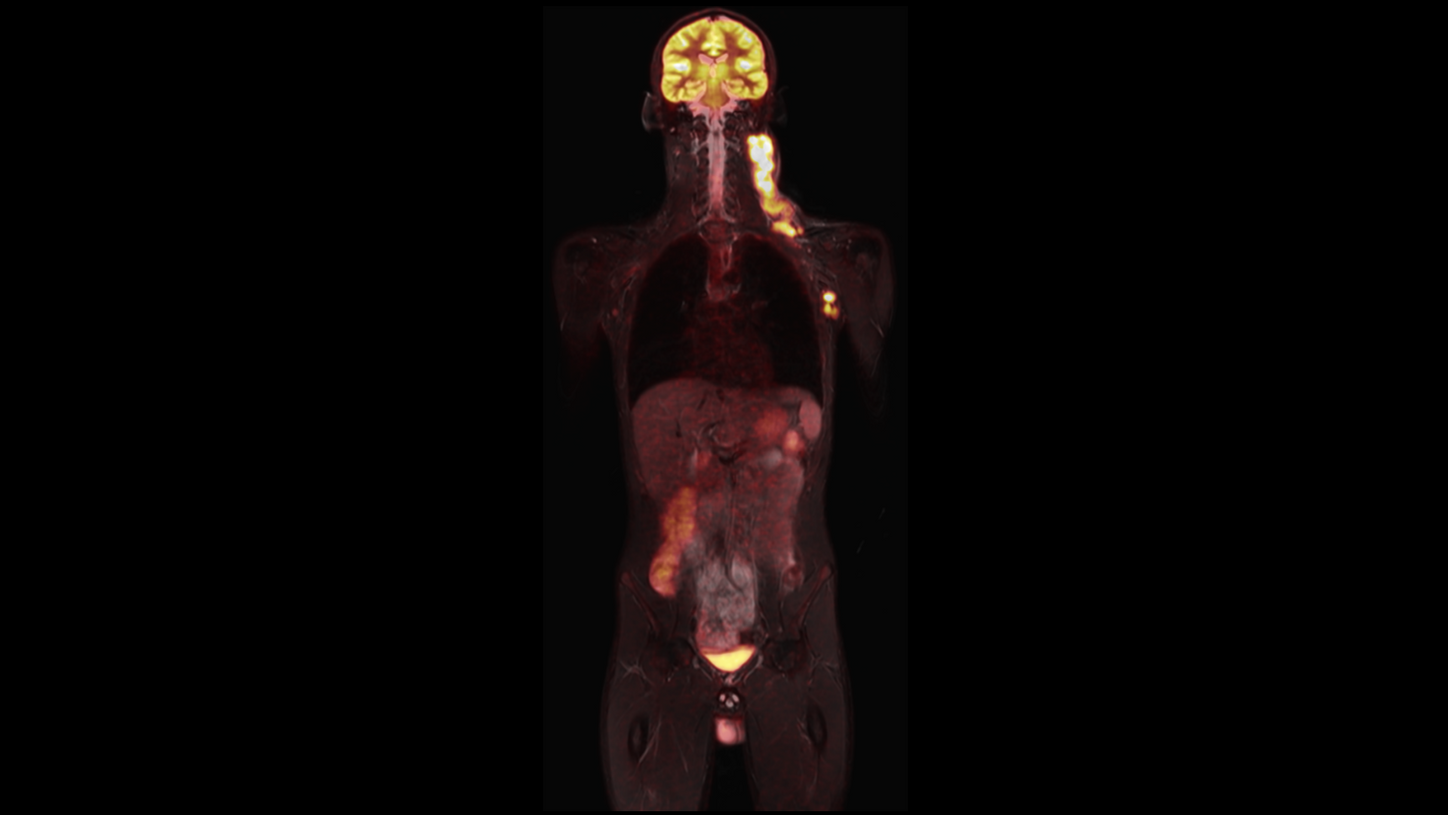

BIOGRAPH One is designed to support one patient-centric pathway to personalized care. By seamlessly integrating PET and MR into one comprehensive exam, it will support clinicians from diagnosis and staging, through a personalized therapy decision to regular therapy assessments to excel precision and support one streamlined approach.

BIOGRAPH One is designed to reduce patient slot times by more than 50 % to under 30 minutes5 for standard whole-body exams, including dedicated brain protocols. With up to 5x faster positioning5 and 2x faster acquisition5 – BIOGRAPH One has the potential to establish PET/MR as a standard clinical modality, aligning patient slot times with typical clinical workflows.